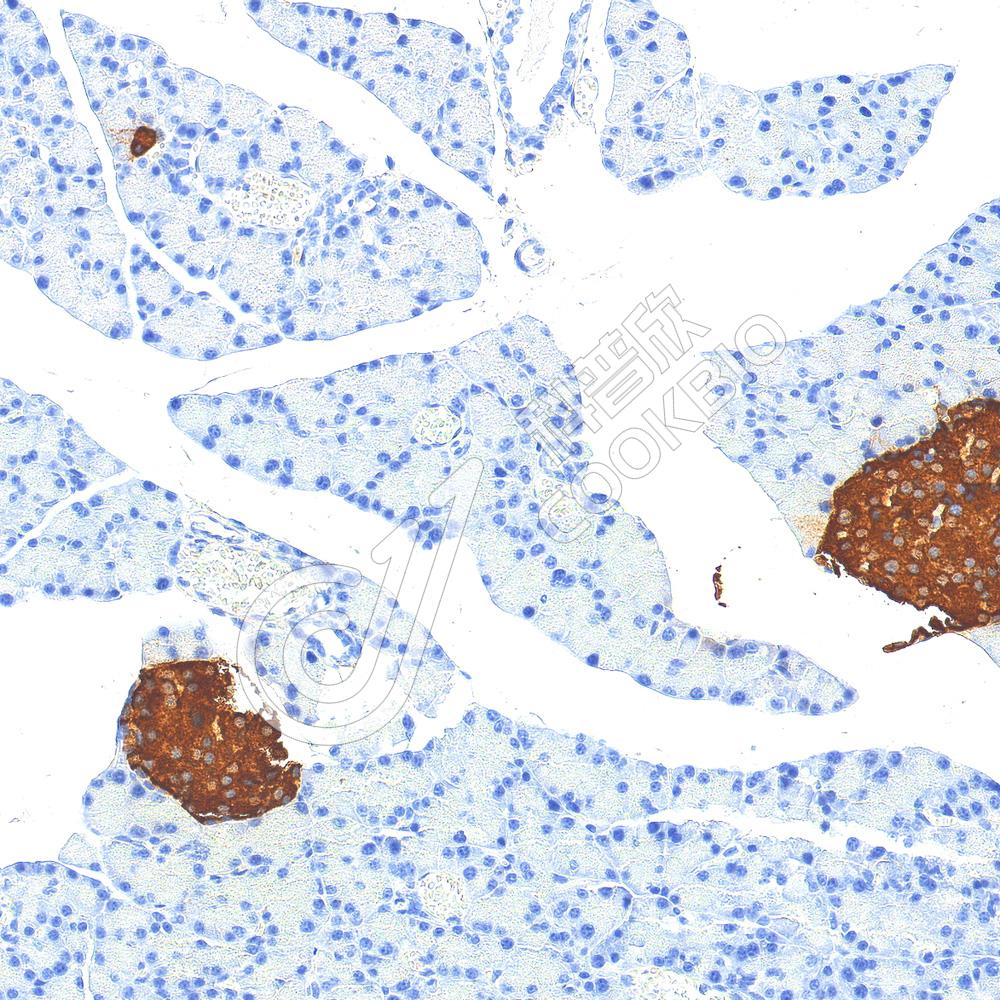

IHC检测ATP5A蛋白(货号 K5460365).

样品: 小鼠肾, 4%多聚甲醛 (货号KSG1101) 固定12-24小时.

抗原修复: Tris-EDTA抗原修复液(pH 9.0) (KSG1203), 100℃, 25分钟.

—抗: 1: 2000稀释, 4℃ 孵育过夜.

二抗: S-vision免疫组化多聚二抗(山羊抗小鼠), 即用型(货号KB3903), 室温孵育20分钟.